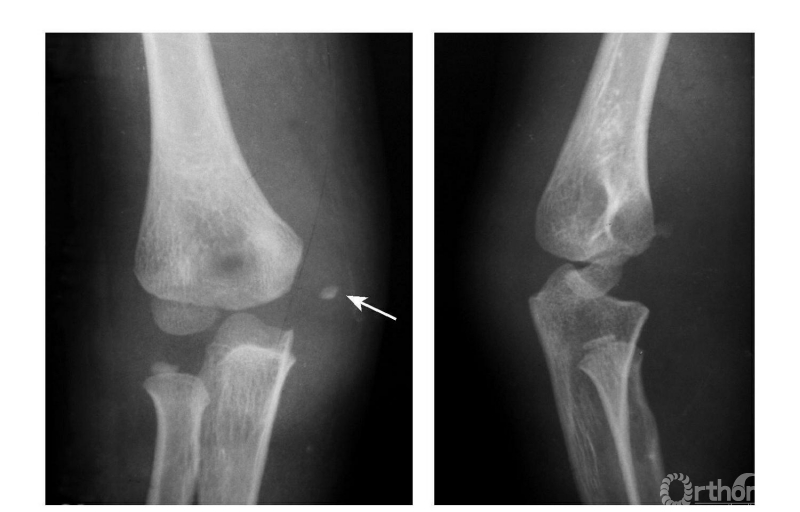

例3:肱骨内上髁Ⅲ度骨折并桡骨颈骨折(歪戴帽)(图8)。

图8

Ⅳ度损伤:

例1:肘关节外后脱位并肱骨内上髁撕脱骨折,骨块移向尺肱关节间(图9)。

图9

例2:肱骨内上髁Ⅳ度骨折并肘关节旋转性脱位(图10)。

图10